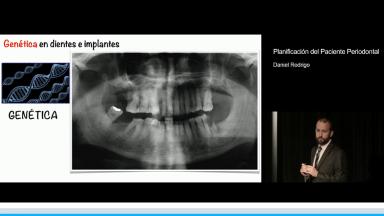

La patología periodontal es un hallazgo muy común en nuestras consultas. Además constituye uno de los factores de riesgo más importantes en el tratamiento implantológico por motivos tan diferentes como son los estéticos, quirúrgicos, biológicos, biomecánicos y hasta filosóficos si tenemos en cuenta el dilema que a veces se nos plantea en la clínica sobre extraer o no extraer y cuándo hacerlo.

En esta conferencia, el Dr. Rodrigo presta especial atención a todos los aspectos de riesgo englobados en el manejo del paciente periodontal en tratamiento con implantes, efectuando una exhaustiva revisión de la evidencia existente y con abundante iconografía. Se revisan factores de riesgo tales como el biológico, incluyendo tanto la genética como la microbiología pasando por el diseño personalizado de la prótesis, el riesgo estético y las limitaciones de nuestro tratamiento respecto a las expectativas de los pacientes y finalmente el riesgo quirúrgico o como simplificar nuestros procedimientos en estos pacientes de alto riesgo, mediante el empleo de implantes cortos, estrechos, angulados e inmediatos.